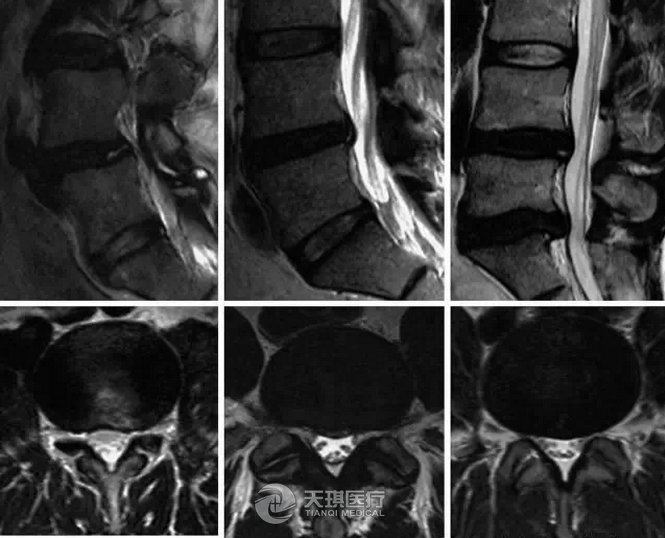

MRI(核磁共振)檢查對于腰椎及其附近組織提供了最為全面的信息,應該對所有懷疑腰椎神經根性病變患者行此檢查(圖4)。MRI的準確性十分高,并且可以識別出可能有發(fā)展為腰椎脊髓病變危險的異常改變。

圖4 纖維環(huán)撕裂的MRI矢狀位(A,C,E)和軸位(B,D,F)T2加權像影像。A和B,放射狀撕裂(箭頭所指)。C和D,同心性撕裂(箭頭所指)。E和F,橫向性撕裂,只能在矢狀位上看見(箭頭所指)。(From Edelman RR, Hesselink JR, Zlatkin MB, Crues JV, editors; Clinical magenetic resonance imaging, ed 3, Philadelphia, 2006, saunders p 2203.)